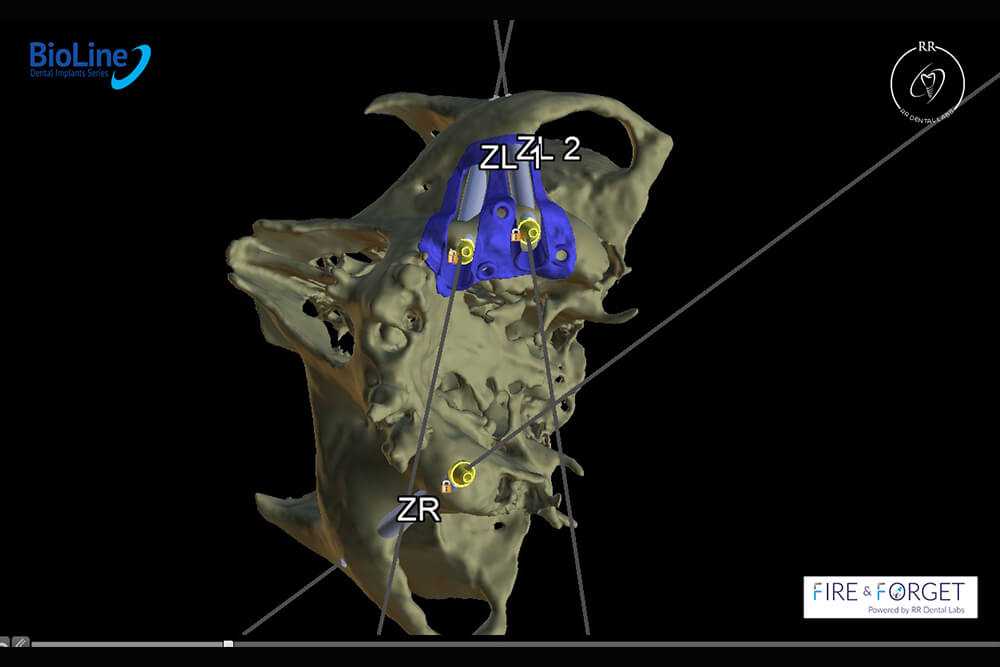

Case 47